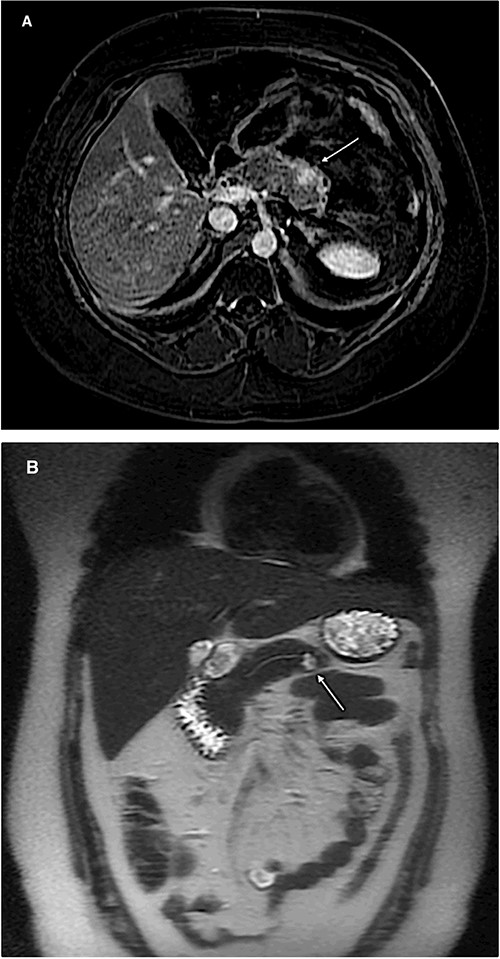

The patient is a 29-year-old female with a history of MEN1, stage II (pT3N0) pancreatic tail neuroendocrine tumor, hyperparathyroidism and recurrent episodes of kidney stones. She underwent a robotic-assisted distal splenopancreatectomy and, after 18 months of follow-up, a magnetic resonance imaging showed a 1 cm lesion in the pancreatic body (Fig. 1A and B). An endoscopic ultrasound reported a 13 × 10 mm solid lesion (Fig. 2). A biopsy was taken, and the histopathology informed a neuroendocrine tumor recurrence.

Magnetic resonance imaging of the abdomen (A: axial section, B: coronal section) showing a 1 cm lesion in the remnant pancreatic body.